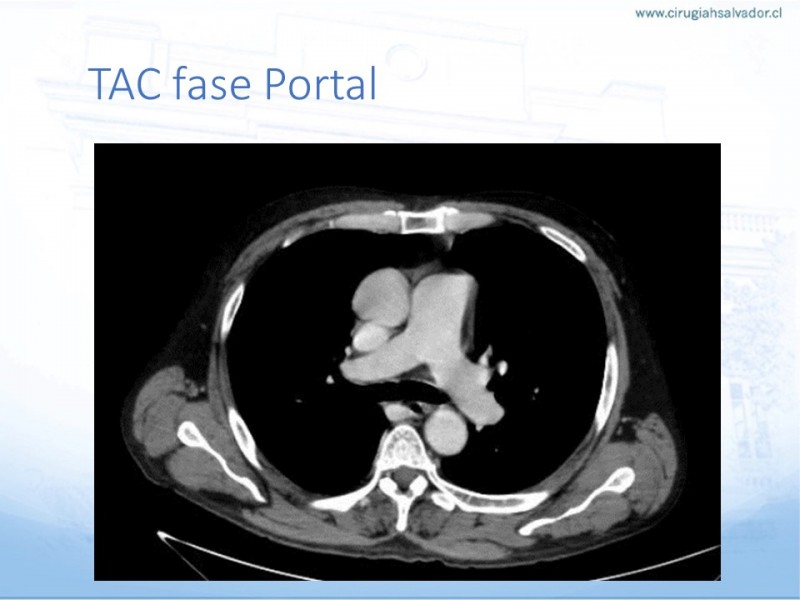

Trombosis Portomesentérica en Cirugía Bariátrica